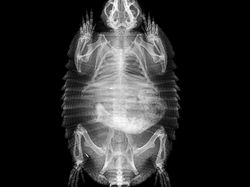

Jakarta - Kebun binatang London dan Oregon merilis foto X-Ray sejumlah hewan-hewannya. Foto tersebut kerap digunakan untuk memantau kondisi kesehatan para hewan.

Deretan Foto X-Ray Para Hewan